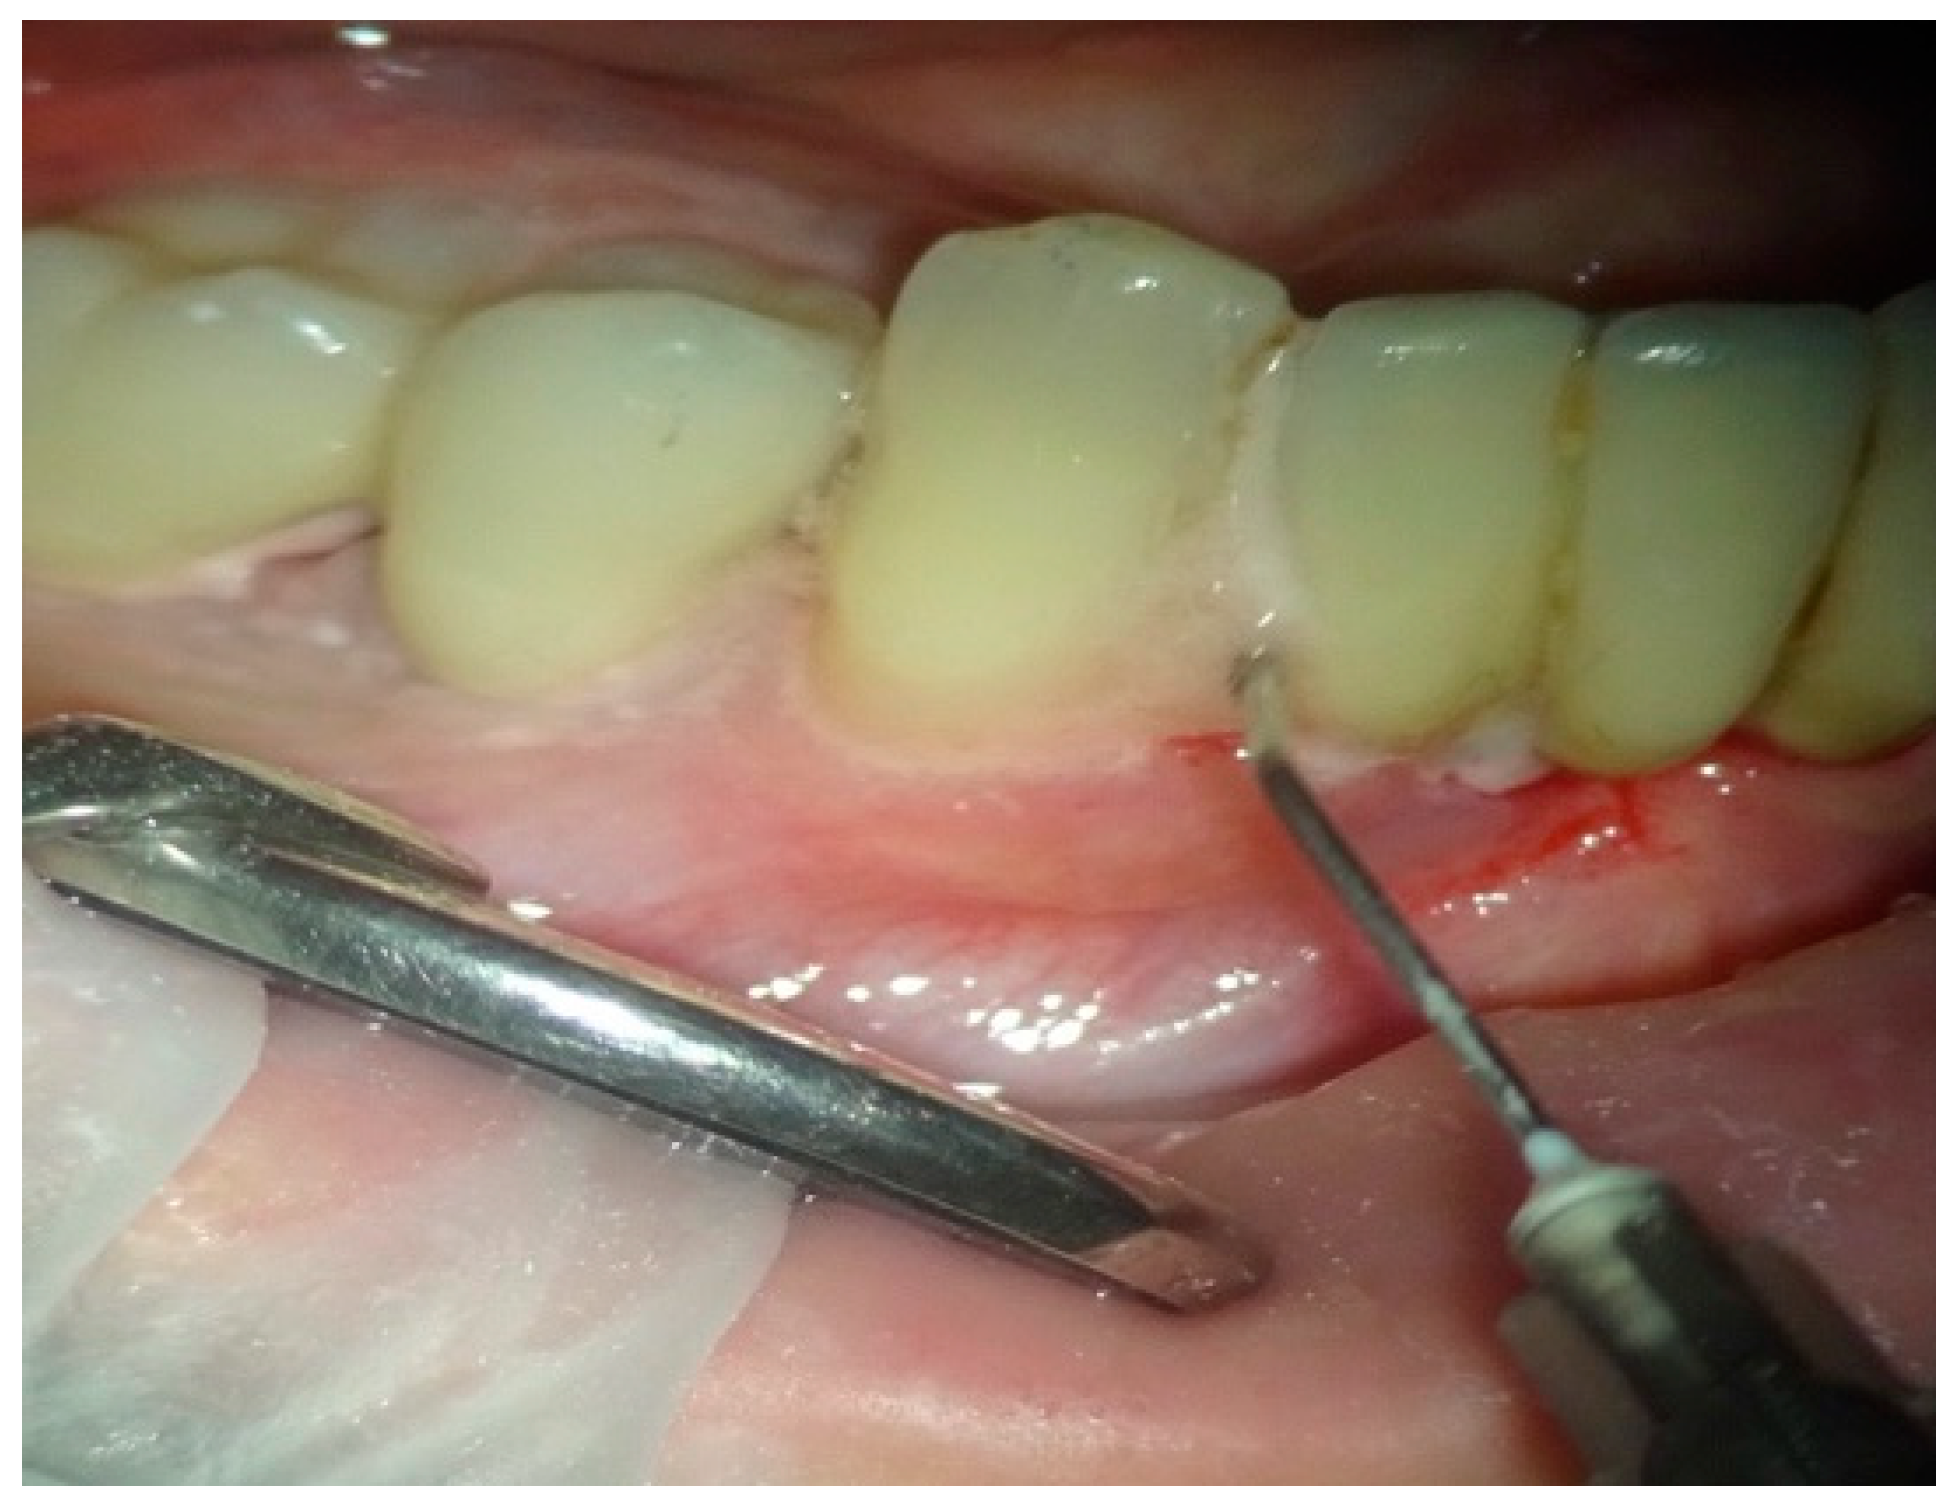

In group B, treated with the OHLLT protocol, a microbiological sampling of the periodontal pockets was made first. Then a supra and subgingival scaling with high-frequency ultrasound was made with a solution of Betadine diluted at 10% (Figure 1). An airflow session with erythritol was performed (Figure 2), and then diode laser treatment with a Sioxyl® solution was performed, irrigating the periodontal pockets with the Sioxyl® solution (Figure 3), leaving the solution for at least 2 min and irradiating with a Wiser diode laser with a peak power of 2.5 W, T-On of 20 microns, T-Off of 80 microns, average power of 0.5 W, duty cycle of 100 microns and frequency of 10 KHz (Figure 4).

Figure 3.

Irrigation with a Sioxyl solution.

Figure 4.

Treatment with a Wiser diode laser with a peak power of 2.5 W, T-On of 20 microns, T-Off of 80 microns, average power of 0.5 W, duty cycle of 100 microns and frequency of 10 KHz.